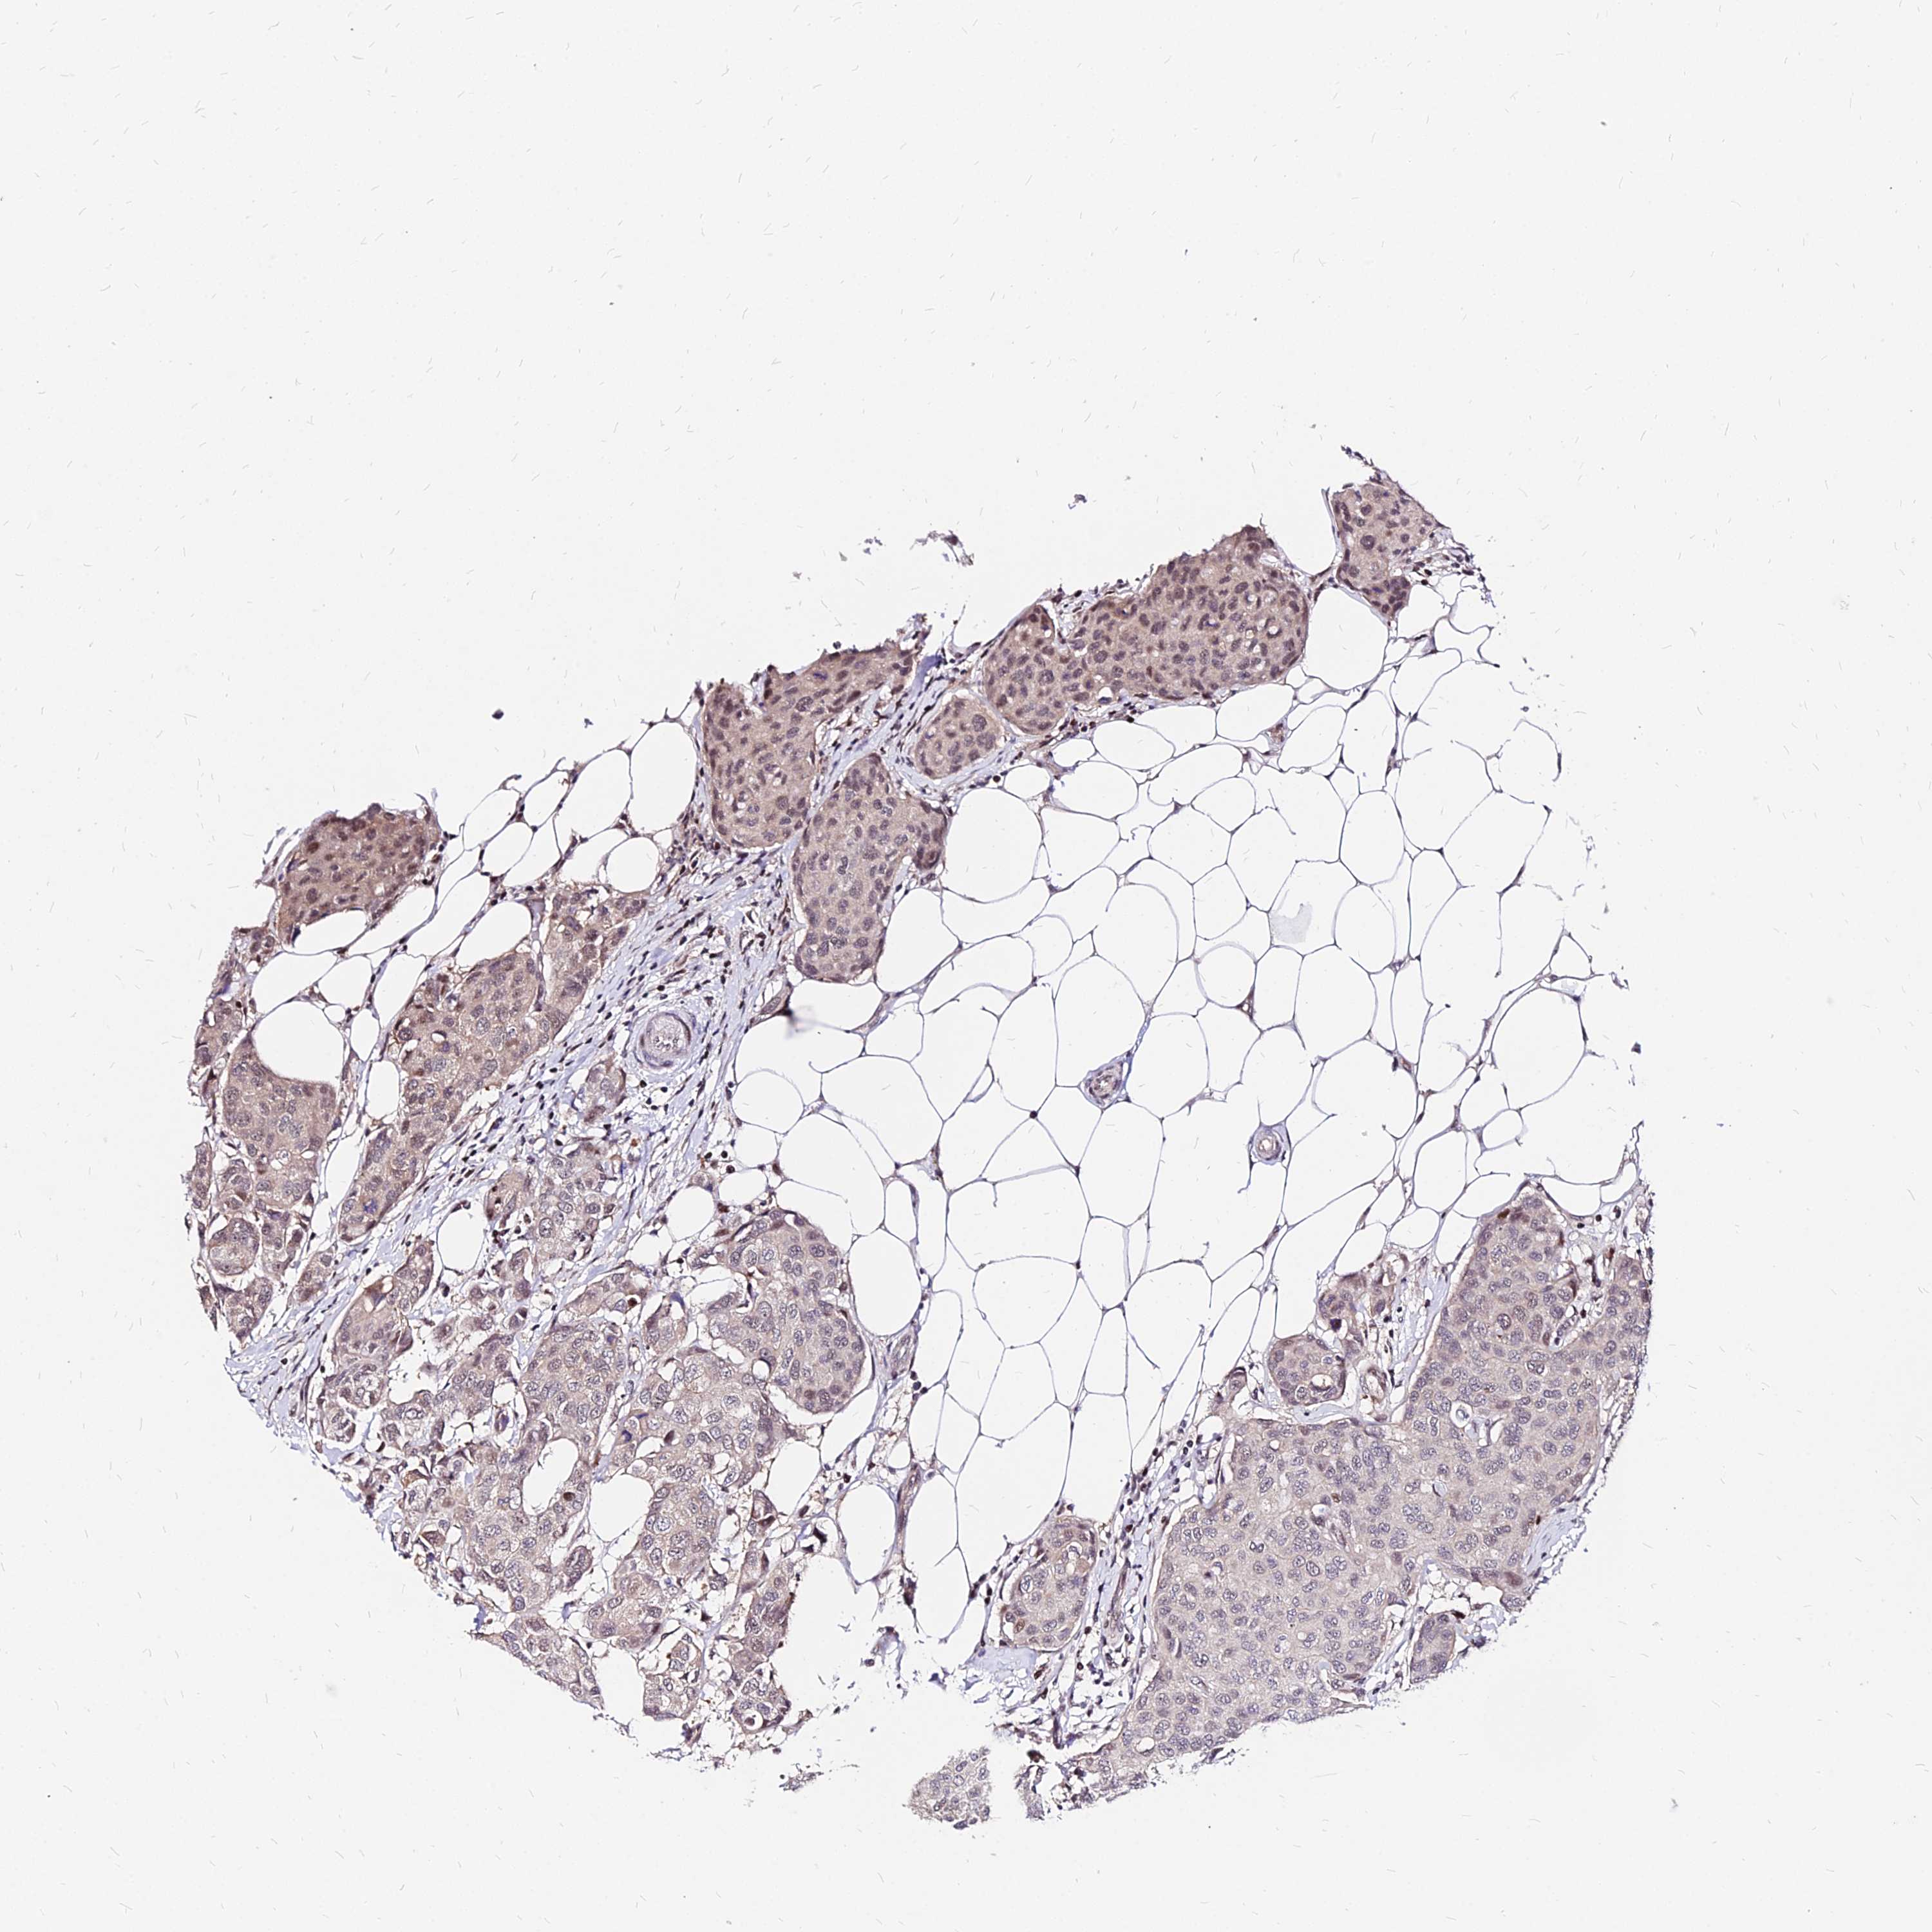

BRCA TCGA BRCA VALIDATION PROTEIN EXPRESSION

Breast cancer

Human cancer